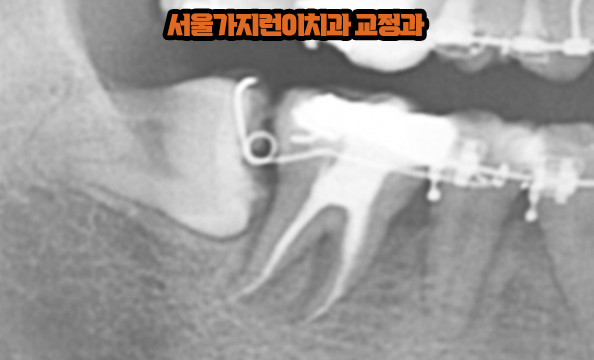

안녕하세요? 서울가지런이치과 교정과 의원입니다. 위 사진은 실제로 저희 치과를 다녀간 환자분의 엑스레이 사진인데요. 보면는 위아래로 사랑니가 나있는 걸 확인할 수 있습니다. 아래의 경우 옆으로 누워있게 났기 때문에 일반적인 치아교정을 했다고 한다면 발치하고 교정을 진행했겠죠. 하지만 사랑니의 모양도 양호한데다 똑바로 세우게 된다면 어금니 역할을 충분히 할 수 있다고 판단이 되었기 때문에 임플란트 대신 치아교정을 통해 구강저작력을 높여볼 수 있었습니다.

네, 가능합니다. 위 사진은 사랑니를 당겨오는 과정인데요. 임플란트와 달리 사랑니는 자연치아기 때문에 치주인대가 일종의 쿠션역할을 해서 저작시 발생하는 충격을 완화해주는데다 지속적으로 힘을 주면 치아이동이 가능하기 때문에 어금니 결손을 해소할 수 있었습니다. 또 사랑니 모습을 보면 보철치료가 들어간 것을 확인할 수 있는데요. 모든 보철치료가 그런 것은 아니지만 치아 위에 씌우는 보철치료후에는 치아교정이 어려울 수 있으니 꼭 치아 손상치료를 하기 전에 교정상담부터 받아보는 걸 권유드립니다.